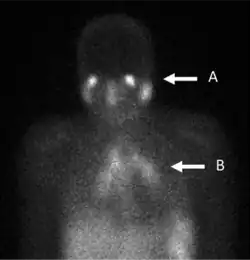

In the past, the gallium scan was the gold standard for lymphoma staging, until it was replaced by positron emission tomography (PET) using 18F-fluorodeoxyglucose (FDG).[7][8] 67Ga-citrate imaging is still used to image inflammation and chronic infections, and it still sometimes locates unsuspected tumors as it is taken up by many kinds of cancer cells in amounts that exceed those of normal tissues. Thus, an increased uptake of gallium-67 may indicate a new or old infection, an inflammatory focus from any cause, or a cancerous tumor.

- Evaluation and follow-up of active lymphocytic or granulomatous inflammatory processes such as sarcoidosis or tuberculosis.[20]

The main (67Ga) technique uses scintigraphy to produce two-dimensional images. After the tracer has been injected, images are typically taken by a gamma camera at 24, 48, and in some cases, 72, and 96 hours later.[21][22] Each set of images takes 30–60 minutes, depending on the size of the area being imaged. The resulting image will have bright areas that collected large amounts of tracer, because inflammation is present or rapid cell division is occurring. Single-photon emission computed tomography (SPECT) images may also be acquired. In some imaging centers, SPECT images may be combined with computed tomography (CT) scan using either fusion software or SPECT/CT hybrid cameras to superimpose both physiological image-information from the gallium scan, and anatomical information from the CT scan.